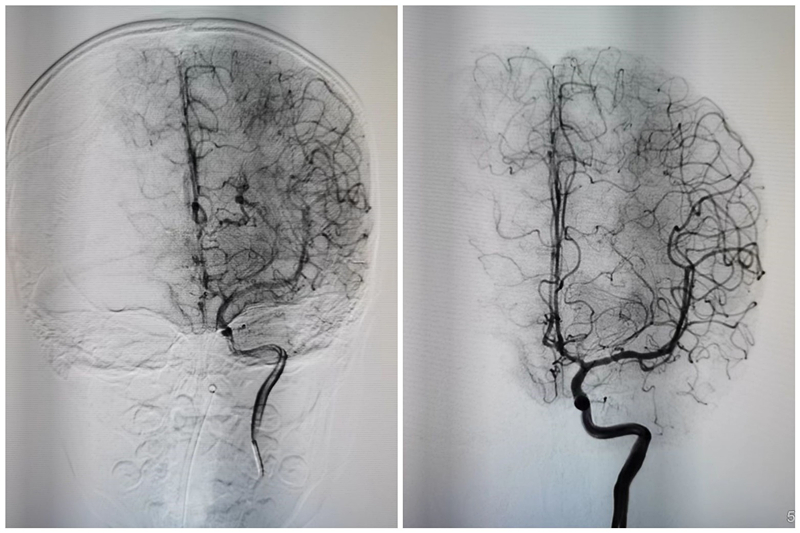

图注:术前术后对比,左侧基底节动静脉畸形合并动脉瘤获得治愈

8岁的患儿是脑血管畸形,因动脉瘤破裂导致脑出血,出现头晕、呕吐、四肢瘫软无力、嗜睡等症状,救护车从敦煌紧急行一千多公里送至兰大二院救治,入院时,患儿已昏迷不醒,小儿重症ICU曹娥英主治医师立即完善相关检查,邀请神经外科医生会诊,为患儿实施锥颅引流术,并给予呼吸机辅助通气,抗感染、抗炎、抗癫痫、镇静等对症治疗。待患儿病情相对稳定后,神经外科三病区主治医师周保元为患儿实施了“局麻下脑动脉造影术+全麻下脑动静脉畸形栓塞术”,术后患儿恢复良好,已治愈出院。

据悉,脑动静脉畸形目前的治疗方式只有三种,开刀手术治疗、介入栓塞治疗及伽马刀治疗。这位小女孩的畸形团在基底节,属于功能区,位置很深,若选择开刀手术治疗,则创伤大,还会对功能有影响,严重的可导致瘫痪或者昏迷;若选择伽马刀治疗,畸形团消退需要一到两年时间,且短期内无法解除出血症状。深思熟虑之下,周保元医生最后选择了介入栓塞治疗方式。

周保元医生说:“小孩手术难度非常大,因为小孩供血动脉的血管天生纤细迂曲,手术用的导管很难通过血管,到达血管远端,加上做造影用的Glubran胶很难控制,手术一次就把动脉瘤和血管畸形彻底清除,并且手术效果超出了预期,女孩完全恢复了正常。手术非常成功,我们很欣慰,替女孩感到开心”。当收到锦旗和感谢信时,周医生说,“作为一名医生,治病救人是职责所在。手术的目的不仅仅是挽救生命,更重要的是在这个基础上要保留患者的神经功能,保障患者的生活质量”。